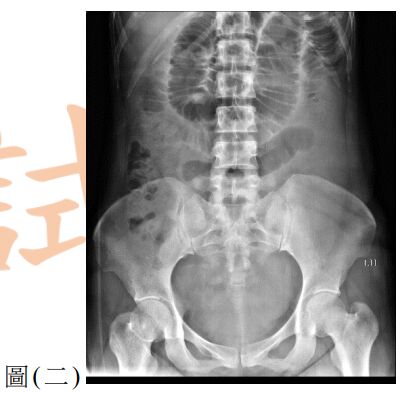

10. 一位60歲女性因腹痛、噁心與嘔吐來急診。此病人有剖腹產與膽囊切除手術病史,其 KUB如圖(二),請問最有可能的診斷為何?

(A) 沾黏性小腸阻塞( adhesive small bowel obstruction ) (B) 大腸阻塞(large bowel obstruction ) (C) 缺血性大腸炎(ischemic colitis) (D) 小腸憩室炎(small bowel diverticulitis)